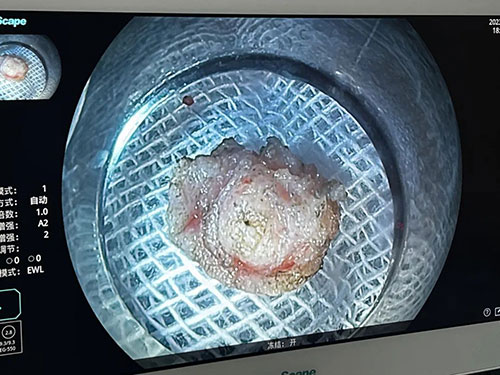

近胡女士感覺(jué)自己大便頻率增多,一天有2-3次,而且性狀也有很大變化。她感覺(jué)很不放心,于是來(lái)我院就診,門(mén)診擬“直腸黏膜隆起”收住入院。在患者與家屬同意下,由我院王林主任為其行內(nèi)鏡黏膜下剝離術(shù)(ESD),手術(shù)順利完成。術(shù)后將術(shù)中切除物送去病理,病理結(jié)果顯示“直腸神經(jīng)內(nèi)分泌腫瘤”。

胡女士做的這項(xiàng)內(nèi)鏡粘膜下剝離術(shù)(ESD),是在內(nèi)鏡下粘膜切除術(shù)(EMR)基礎(chǔ)上發(fā)展而來(lái)的新技術(shù),治療主要針對(duì)早期消化道癌和癌前病變。

方法是在內(nèi)鏡粘膜下注射基礎(chǔ)上利用幾種特殊的高頻電刀,將病變所在粘膜剝離。切除深度:粘膜全層,粘膜肌層及大部分粘膜下層。

通過(guò)ESD可完整地切除病變,達(dá)到治療消化道腫瘤的效果。